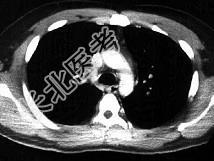

- 单项选择题男,28岁, 突发呼吸困难,结合影像图像, 选择最可能的诊断 ( )

A、右上肺大叶性肺炎

B、右上肺奇叶

C、右主肺动脉栓塞

D、右肺中央肺癌并右上肺不张,淋巴转移

E、右上肺小叶性肺炎